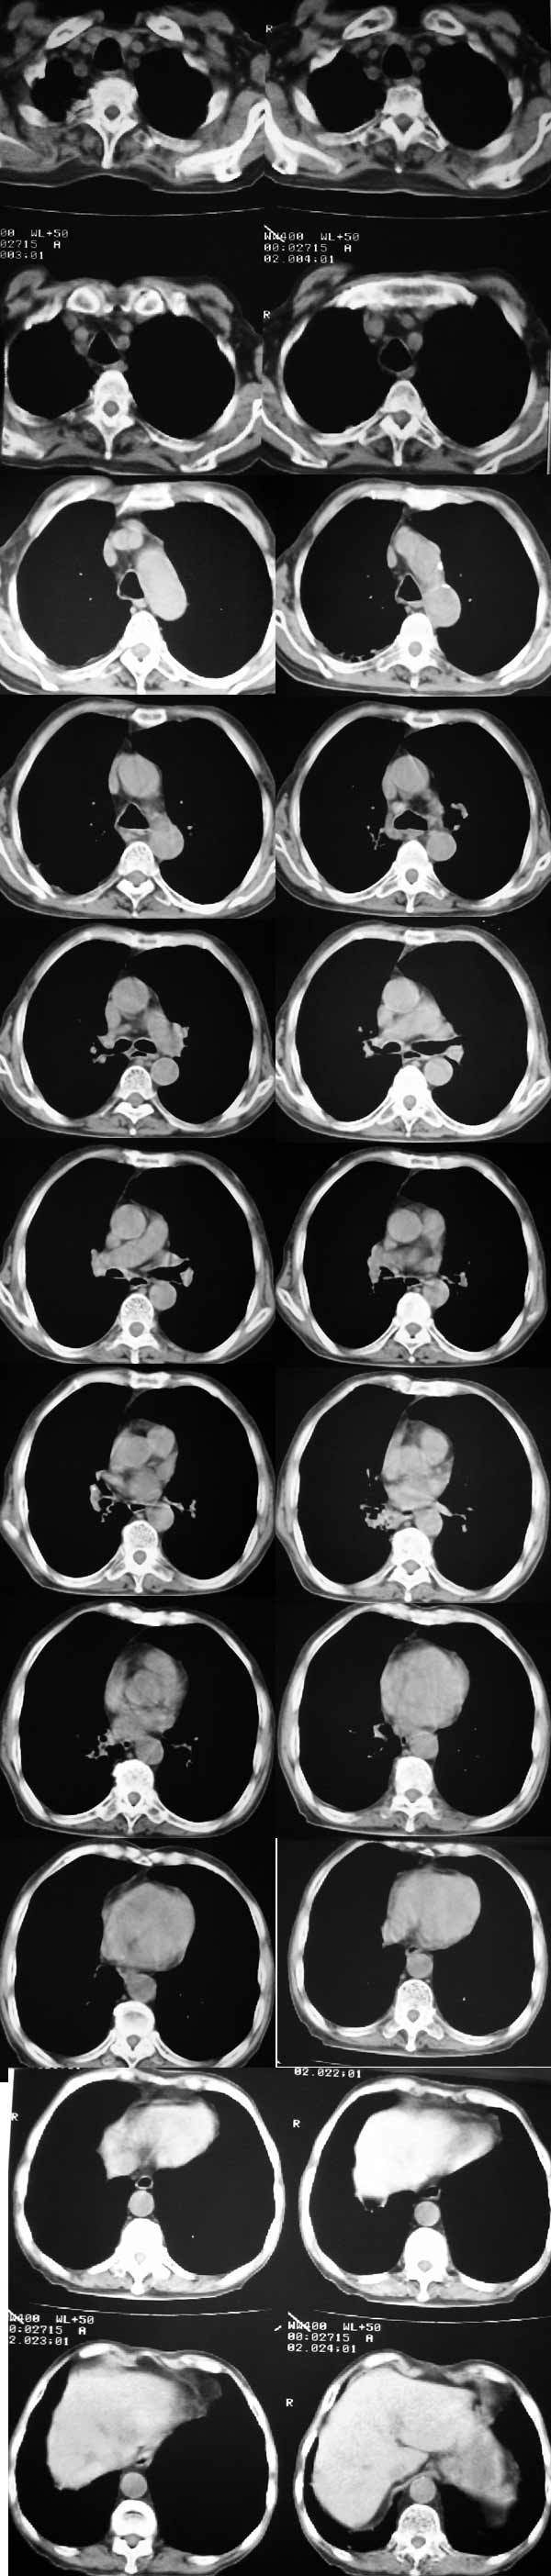

右肺下叶沿着支气管根部见不规则软组织密度影,支气管壁不规则增厚,增强轻度强化.患者年龄偏大,结合临床:多考虑:支气管内膜癌.

右肺下叶沿着支气管根部见不规则软组织密度影,支气管壁不规则增厚,增强轻度强化.患者年龄偏大,结合临床:多考虑:支气管内膜癌.病人已经抗炎治疗4个月了,再抗炎治疗也是这样。

1、右肺感染性病变;

2、右肺间质纤维化;

3、肺气肿;

4、符合右下肺支气管扩张;

5、纵隔淋巴结肿大;

6、右侧肺门气食隐窝处似有不规则肿块,内密度不均,可以随访或纤支镜检查除外肿瘤。